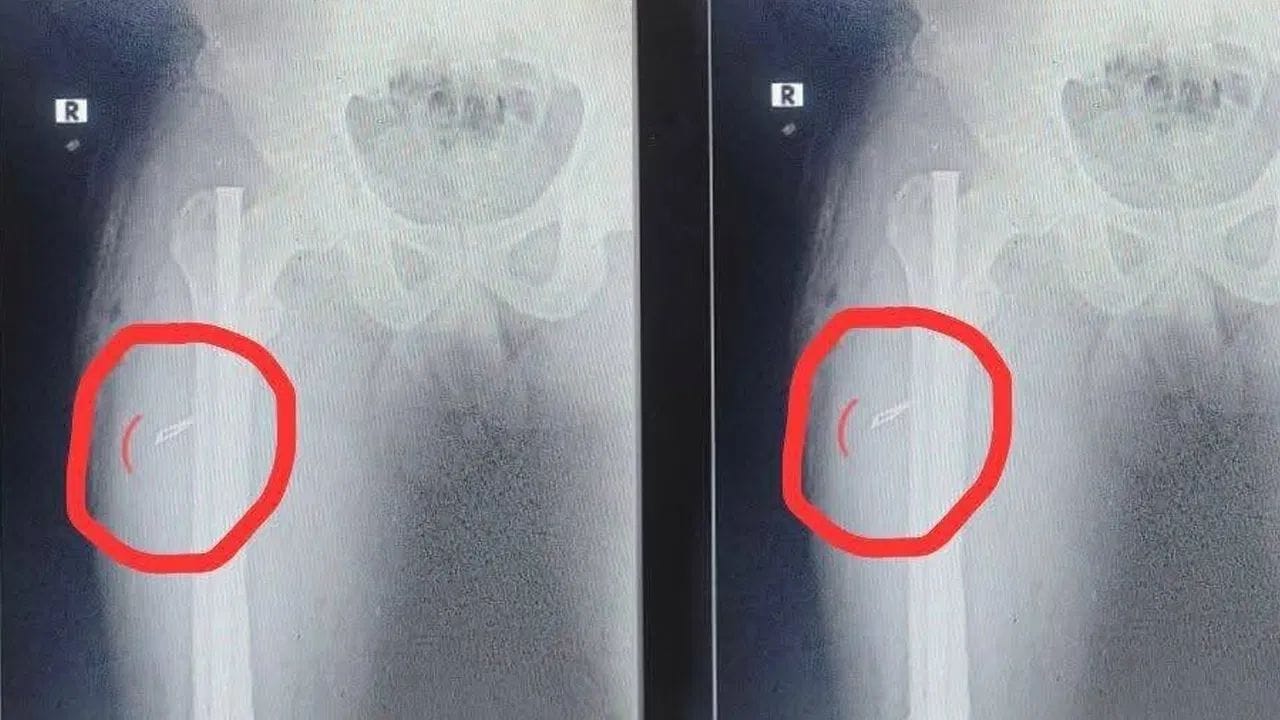

ಬೋಲ್ಟ್ ತೆಗೆಯಲು ಟುನಿ ಸರ್ಕಾರಿ ಆಸ್ಪತ್ರೆ ವೈದ್ಯರು ಎಲ್ಲ ತಯಾರಿ ಮಾಡಿಕೊಳ್ಳುತ್ತಿದ್ದ ವೇಳೆ, ಅವರಿಗೆ ಮತ್ತೊಂದು ಅಚ್ಚರಿಯ ವಸ್ತುವೊಂದು ಕಾಲಿನಲ್ಲಿ ಕಂಡಿದೆ. ಒಂದು ವರ್ಷದ ಹಿಂದೆ ಮಾಡಿದ ಶಸ್ತ್ರಚಿಕಿತ್ಸೆ ವೇಳೆ, ವೈದ್ಯರು ಶಸ್ತ್ರಚಿಕಿತ್ಸಾ ಬ್ಲೇಡ್ನ್ನು ಕಾಲಿನ ಒಳಗೆಯೇ ಬಿಟ್ಟಿದ್ದಾರೆ. ಇದೀಗ ಅದನ್ನು ತೆಗೆದು ಮತ್ತೆ ಹೊಲಿಗೆ ಹಾಕಿದ್ದಾರೆ. ಇದರಿಂದ ಆಸ್ಪತ್ರೆ ಸಿಬ್ಬಂದಿ ಎಷ್ಟು ಬೇಜವಾಬ್ದಾರಿಯಿಂದ ವರ್ತಿಸಿದ್ದಾರೆ ಎಂಬುದು ಕಾಣುತ್ತಿದೆ ಎಂದು ರೋಗಿಯ ಮನೆಯವರು ಹೇಳಿದ್ದಾರೆ. ಇನ್ನು ವಿಚಾರ ತಿಳಿದು ರೋಗಿ ಕೂಡ ಬೇಸರ ವ್ಯಕ್ತಪಡಿಸಿದ್ದಾರೆ. ಈ ಬಗ್ಗೆ ವೈದ್ಯರು ಬಳಿ ಕೇಳಿದಾಗ, ವೈದ್ಯರು ರೋಗಿಯ ವಿರುದ್ಧವೇ ಮಾತನಾಡಿದ್ದಾರೆ.

ನೀವು ನಮ್ಮನ್ನು ಪ್ರಶ್ನೆ ಮಾಡಬೇಡಿ, ಈ ಬಗ್ಗೆ ನಮಗೆ ಗೊತ್ತಿಲ್ಲ ಎಂದು ಹೇಳಿದ್ದಾರೆ. ರೋಗಿಯ ಕಾಲಿನಿಂದ ಶಸ್ತ್ರಚಿಕಿತ್ಸಾ ಬ್ಲೇಡ್ನ್ನು ಹೊರ ತೆಗೆದು ಹೊಲಿಗೆ ಹಾಕಿರುವುದು, ಭಾರೀ ಚರ್ಚೆ ಕಾರಣವಾಗಿದೆ. ಅದರೂ ವೈದ್ಯರ ಕಡೆಯಿಂದ ತಪ್ಪಾಗಿದೆ ಎಂಬುದನ್ನು ಒಪ್ಪಿಕೊಳ್ಳಲು ತಯಾರಿರಲಿಲ್ಲ. ಸರ್ಕಾರಿ ಆಸ್ಪತ್ರೆಗಳ ವೈದ್ಯರ ಕಾರ್ಯಕ್ಷಮತೆಯ ಬಗ್ಗೆ ನೆಟ್ಟಿಗರು ಪ್ರಶ್ನಿಸಿದ್ದಾರೆ. ಈ ಕಾರಣಕ್ಕೆ ಜನ ಸರ್ಕಾರಿ ಆಸ್ಪತ್ರೆಗಳಿಗೆ ಬರಲು ಎದರುತ್ತಿದ್ದಾರೆ ಎಂದು ನೆಟ್ಟಿಗರು ಸೋಶಿಯಲ್ ಮೀಡಿಯಾದಲ್ಲಿ ಕಮೆಂಟ್ ಮಾಡಿದ್ದಾರೆ.